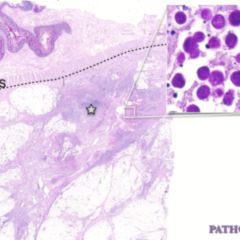

La pared de los órganos huecos del aparato digestivo como el esófago, estómago, intestino delgado e intestino grueso, está formada por varias capas, las principales de dentro a fuera son mucosa que es la que está en contacto con los alimentos y sustancias procedentes de la digestión, muscularis propia y serosa. Entre la mucosa y la muscularis propia se sitúa la submucosa y entre la muscularis propia y la serosa se encuentra la capa subserosa. Estás capas son muy importantes en oncología, ya que los tumores digestivos suelen originarse en la capa mucosa e invaden progresivamente las demás capas hasta llegar a la subserosa y serosa.[1] [2]